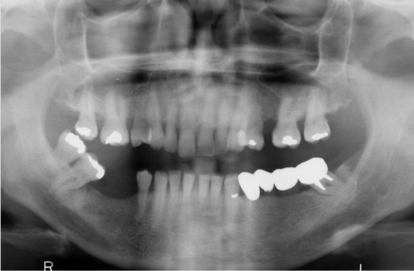

Nel prossimo case report presenteremo un follow-up a 9 anni dall’inserimento di una fixture GTB di 4,3 mm di diametro e 6 mm di lunghezza, in posizione 36, come elemento di ponte di una riabilitazione protesica 34-36,dove in posizione 34 abbiamo una fixture GTB3.6 mm di diametro e 9mm di lunghezza.